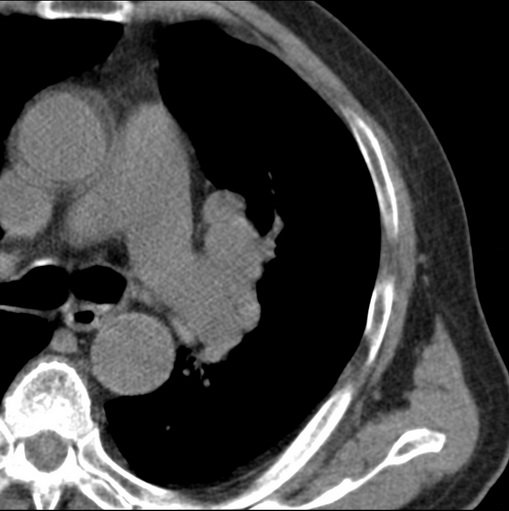

男性患者 81岁 咳嗽 咳痰 咯血

有强化 考虑肺癌肺门淋巴结转移

考虑左上肺癌并阻塞性肺炎,左肺转移、左肺门及纵隔淋巴结转移。

支持左侧中央型肺癌伴肺门及纵膈淋巴结转移。

肿块贴近左肺门,包绕左上肺动脉,形态不规则。肿块增强扫描中度强化。纵膈内主动脉弓左旁间隙、气管隆突前、下间隙见多枚淋巴结影。综上考虑左侧中央型肺癌可能性大。图片没有完整上传,尤其是左肺上叶支气管分支层面没有上传,因此不好判断是叶支气管中断还是段支气管中断。另外,下图红色部分所示是“黏液支气管征”吗?